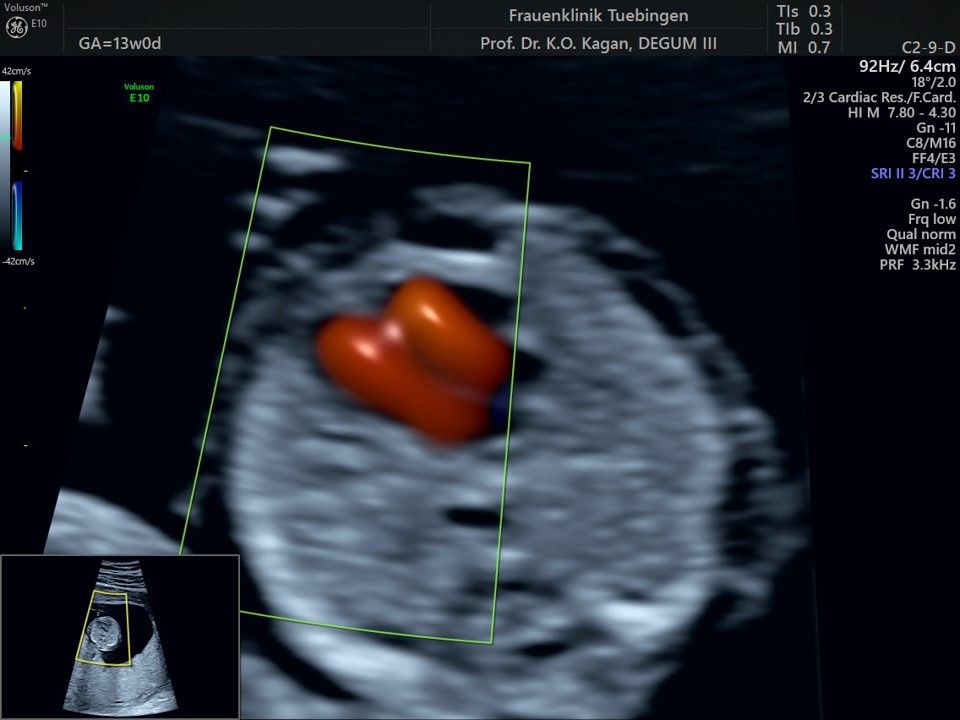

Herz